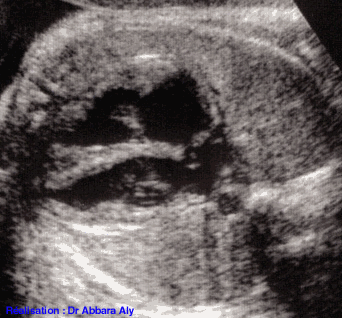

Coupe des quatre cavités cardiaques